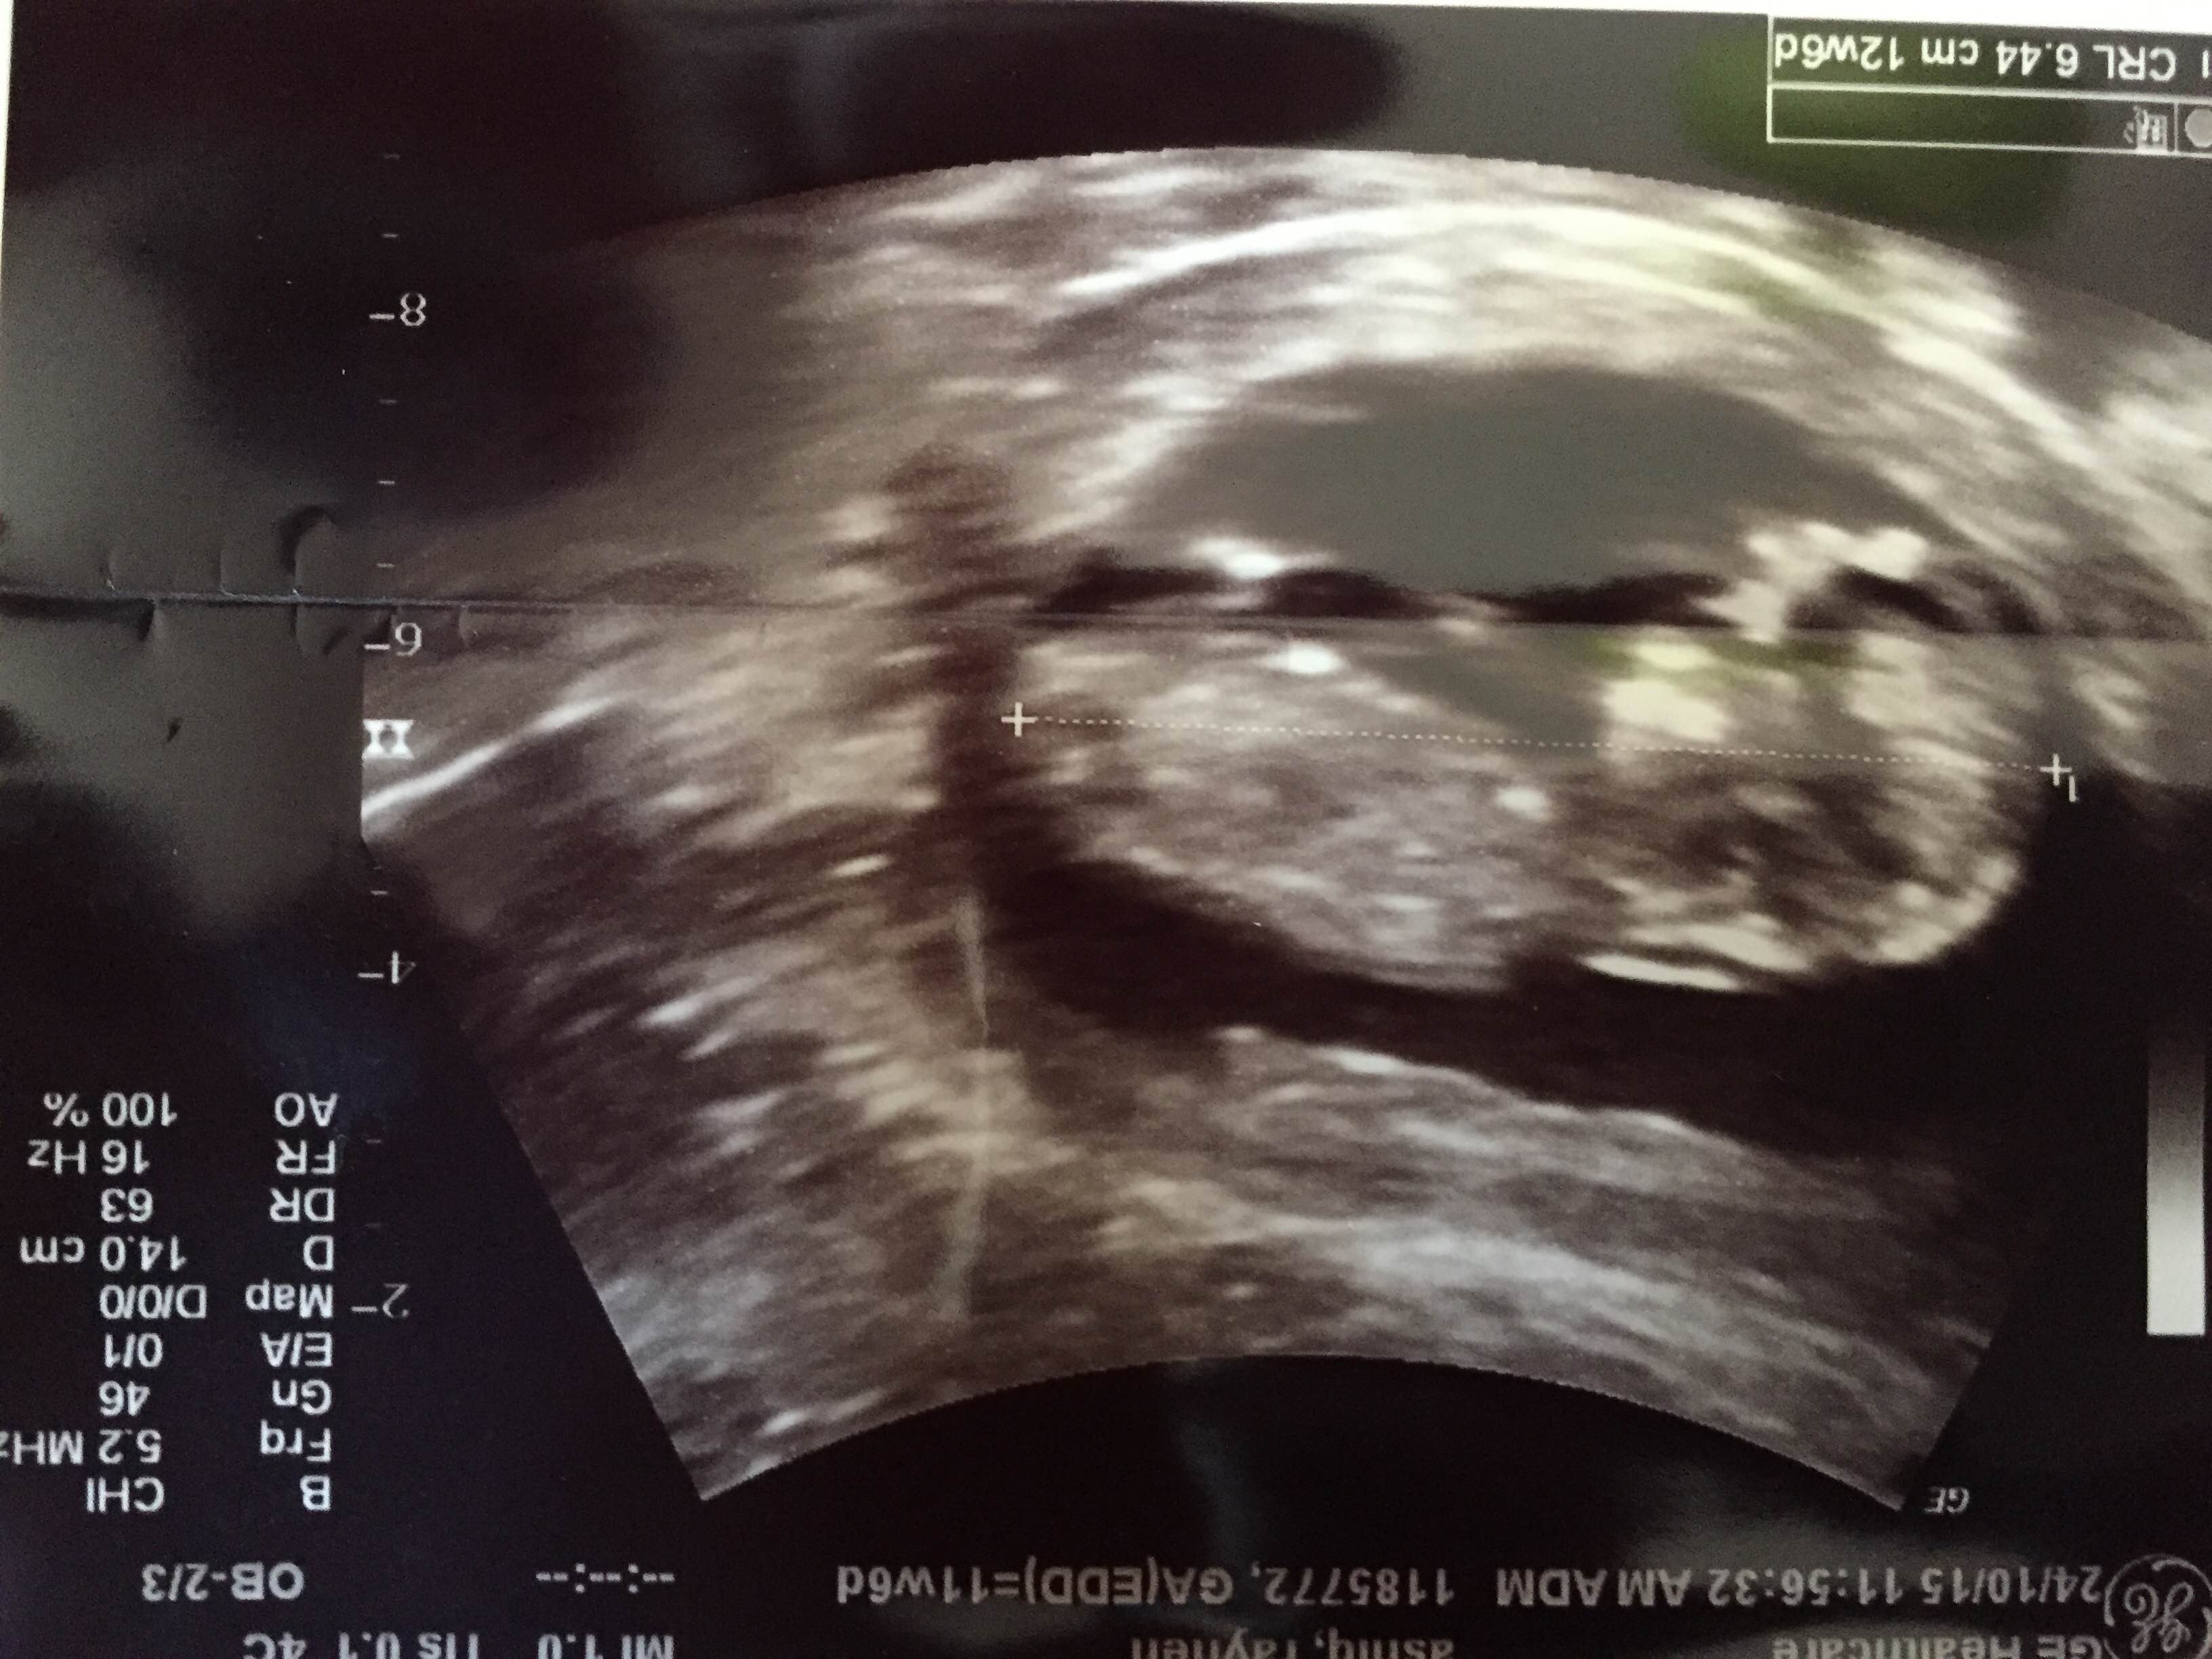

No nub, sorry.

Thanks ...do you think it still needs time to figure out the nub and gender ??